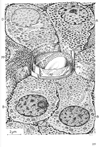

消化器;消化器系【しょうかきけい】(栄養分を取りこむ器官系で、言い換えれば、身体の成長に必要な物質と身体の活動を支えるためのエネルギー源とを取り入れるのが消化器の役割である。消化器は口腔・咽頭・食道・胃・小腸・大腸などから構成された「消化管」とこれに開く唾液腺・肝臓・膵臓などの「消化腺」とから出来ている。)